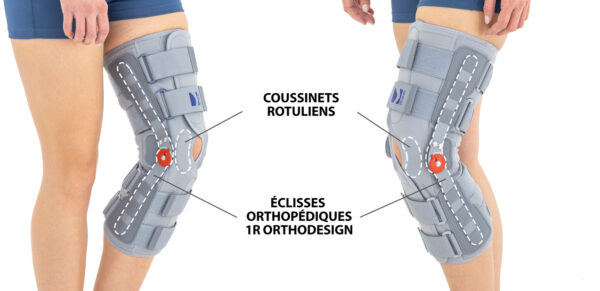

Orteza zapewnia doskonałą stabilizację boczną dzięki dwóm szynom z zegarem 1R umożliwiającym regulację kąta zgięcia i wyprostu co 15 stopni. Zegar ten pozwala na zwalczanie przykurczów w stawie oraz biernie wspomaga proces rehabilitacji.

W celu dokładniejszego dopasowania, a co za tym idzie większej stabilizacji kończyny dolnej, wprowadziliśmy do naszych ortez stawu kolanowego szyny wyprofilowane typu 1R orthodesign. Zastosowanie takiego typu przeprofilowania szyny umożliwia utrzymanie zawiasów w osi zgięcia stawu kolanowego podczas fizjologicznego zginania stawu kolanowego.

Każda orteza z serii IB jest wyposażona w dwie wyprofilowane peloty które wzmacniają i stabilizują rzepkę.

Orteza zapewnia doskonałą stabilizację boczną dzięki dwóm szynom z zegarem 1R umożliwiającym regulację kąta zgięcia i wyprostu co 15 stopni. Zegar ten pozwala na zwalczanie przykurczów w stawie oraz biernie wspomaga proces rehabilitacji.

W celu dokładniejszego dopasowania, a co za tym idzie większej stabilizacji kończyny dolnej, wprowadziliśmy do naszych ortez stawu kolanowego szyny wyprofilowane typu 1R orthodesign. Zastosowanie takiego typu przeprofilowania szyny umożliwia utrzymanie zawiasów w osi zgięcia stawu kolanowego podczas fizjologicznego zginania stawu kolanowego.

Każda orteza z serii IB jest wyposażona w dwie wyprofilowane peloty które wzmacniają i stabilizują rzepkę.